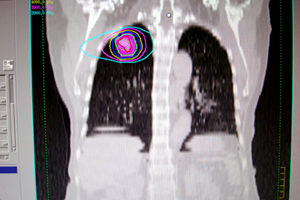

謝小姐是一名上班族,去年5月手指指尖有麻感,但1個月後竟整隻手指到手臂都麻,至國泰醫院就醫檢查後診斷也是「頸脊髓病變」。(圖:醫師說明謝小姐開刀部位)

張主任說,「頸脊髓病變」大都需藉由外科手術來治療,一般的復健治療幫助有限,由於頸部非常脆弱及重要,慢性勞損外傷或老化退變導致頸段血管神經繼發性損傷而發病。因此當民眾患有頸部酸痛以及手發麻的現象時,不要掉以輕心以為沒什麼關係,因為它往往是頸椎退化性病變的先兆。一定要先接受醫師的診斷和放射線檢查,才可以決定何種治療。如果沒有明確的骨骼及神經的病變,再來接受治療,這樣才較能有安全的保障及療效。如果已經有明確的病變則應該儘早與醫師討論,以尋求正確的治療,以免延誤病情,而造成無可挽回的後遺症。(右圖:吳先生從事食品業,頸椎過度使用)